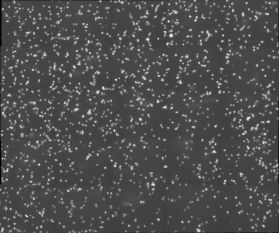

明美活細胞掃描分析儀(yi) MCS31助力北京眼科研究所小鼠巨噬細胞觀察

北京眼科研究所致力於(yu) 探索眼科疾病的發病機製和治療方法,其中免疫學研究是其重要方向之一。在一項關(guan) 於(yu) 小鼠巨噬細胞的研究中,科研人員需要對細胞進行長時間的動態監測,以觀察其在免疫反應中的行為(wei) 變化。然而,傳(chuan) 統的顯微鏡在長時間成像時往往麵臨(lin) 成像速度慢、清晰度不足以及軟件操作複雜等問題,這些問題嚴(yan) 重限製了研究的進展。

MCS31配備了10XPH20PH高分辨率物鏡,能夠提供清晰、細膩的細胞圖像,滿足基本的細胞成像需求。

活細胞掃描分析儀(yi) MCS31憑借其高清晰度成像、快速成像能力和穩定的長時間監測性能,成為(wei) 了北京眼科研究所攻克小鼠巨噬細胞觀察難題的得力助手。未來,必威betway88欢迎你將繼續致力於(yu) 顯微成像技術的研發與(yu) 創新,進一步優(you) 化產(chan) 品性能,提升用戶體(ti) 驗,為(wei) 更多科研機構提供高效、可靠的顯微鏡解決(jue) 方案。